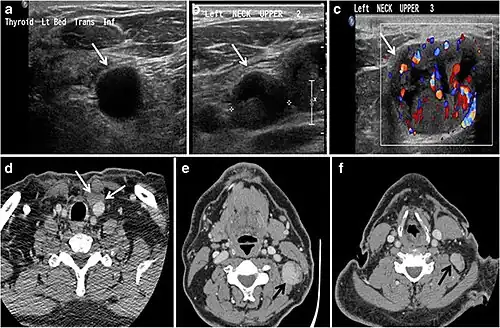

Fig. 7. A 51-year-old female patient post total thyroidectomy for PTC with elevated thyroglobulin measurement. an Axial non-enhanced CT scan of the neck at the level of the thyroid bed demonstrates a well-defined, rounded, homogenously dense soft tissue situated between the trachea and left internal jugular vein (white arrow). b Transverse ultrasound image of the neck demonstrates a well-defined, homogeneous, hypoechoic soft tissue nodule measuring 6 mm (white arrow) with no detected micro-calcifications. Biopsy showed a predominantly residual normal thyroid tissue with micro-foci of PTC.[1]

Fig. 8. A 48-year-old male patient post total thyroidectomy with PTC recurrence. a Transverse greyscale ultrasound of the neck demonstrates a left thyroid bed heterogeneous, predominantly hypoechoic irregular lesion with calcifications (white arrow). b A spot image of iodine 123 total body scan of the neck demonstrate a focus of abnormal radiotracer uptake at the left thyroid bed (Black arrows) between the annotated markers. c Enhanced axial CT scan of the neck demonstrates an enhancing large left thyroid bed mass (white arrow) with no calcifications. The lesion exerts a mass effect on the oesophagus (black arrow) and is inseparable from the trachea.[1]

Fig. 9. A 58-year-old male patient with persistence PTC at thyroid bed with hypervascular nodal metastasis. a–c Transverse greyscale and colour Doppler neck ultrasound demonstrate hypoehoic soft tissue in the left thyroid bed (white arrow in a). There are a heterogeneous enlarged lymph nodes at level 2 and 3 with markedly increased vascularity (white arrow in b and c). d–f Enhanced axial CT images of the neck demonstrate a 2.7 × 1.4 cm hypodense soft tissue lesion anterior to the left carotid sheath (white arrow). There are left-sided enhancing abnormal and enlarged lymph nodes at cervical level 2 and 3 (black arrows).[1]